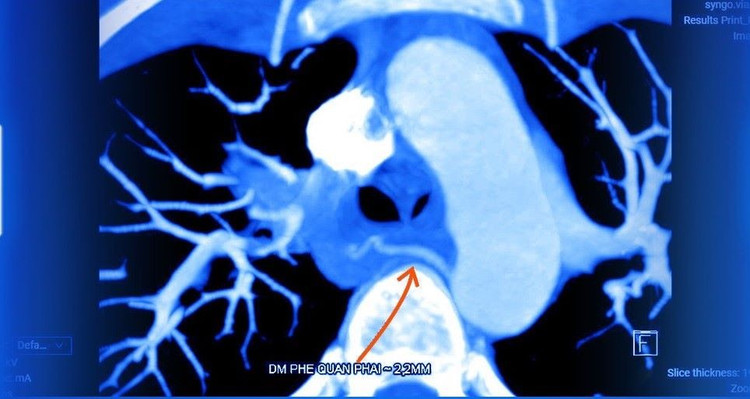

ThS.BSNT Trần Duy Hưng, khoa Hô hấp, Bệnh viện Đa khoa Tâm Anh Hà Nội cho biết, kết quả chụp cắt lớp vi tính cho thấy thùy trên phổi phải xuất hiện các đám đông đặc, kính mờ, dấu hiệu điển hình của tổn thương lao.

Đồng thời, động mạch phế quản phải và nhánh mạch dưới đòn phải giãn ngoằn ngoèo, bất thường. Đây là tình trạng giãn mạch phế quản do lao phổi, hiếm gặp ở người trẻ tuổi, đặc biệt khi không có tiền sử bệnh hô hấp mạn tính. Tổn thương còn lan đến cột sống, nghi do lao.

Hình ảnh CT giãn động mạch phế quản - Ảnh BVCC